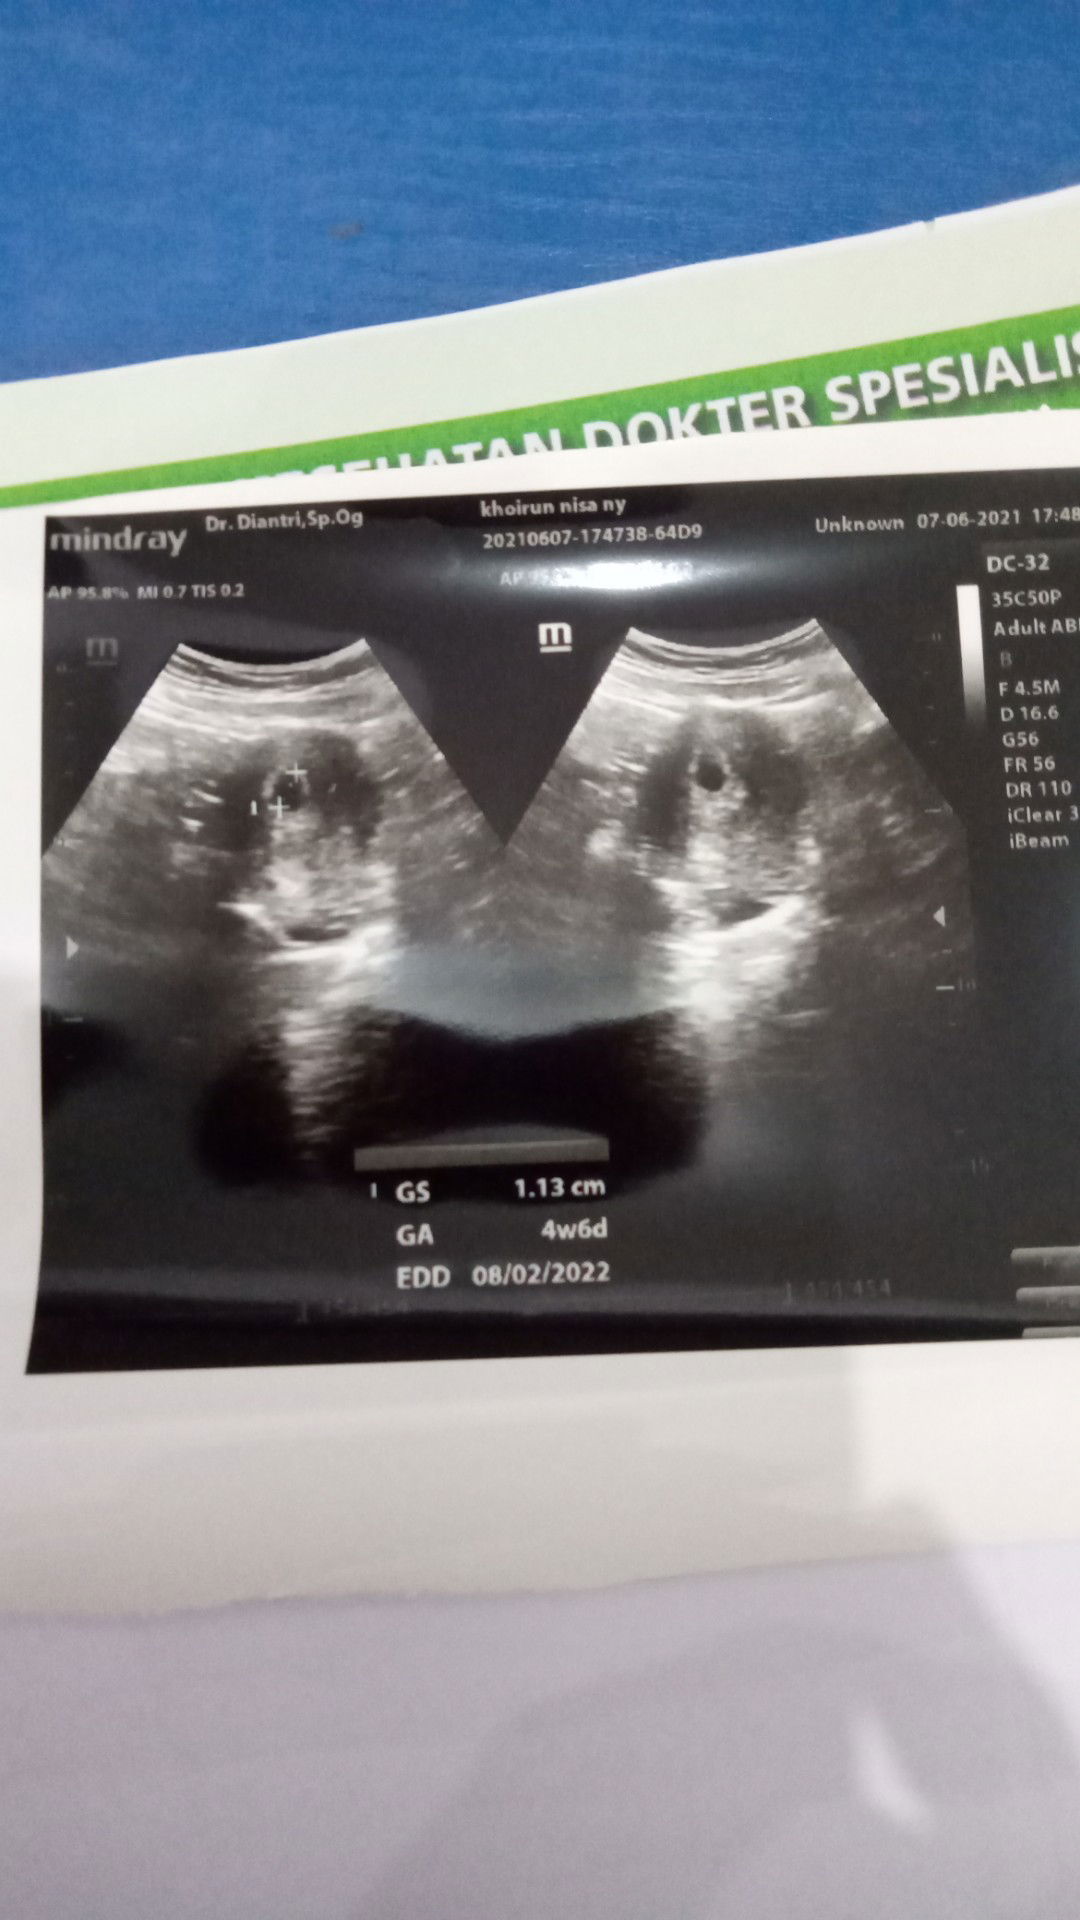

Tes kehamilan

Apakah saya benar benar hami?